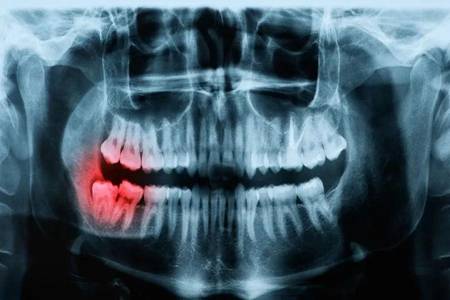

如果你觉得智齿对于口腔问题没有影响,那么就可以不用去拔掉啊。但若是,智齿发炎肿痛的话,还不去拔?等着过年?

一时的疼痛要比一生时不时滋滋的疼好受吧?而且拔牙也没那么疼,第一步就给你上了麻醉,再加上现在的麻药工具也是在不断地更新,所以说只需要配合医生的操作,真的不是很疼。

看到这里,你可能要跃跃欲试的去拔牙了?别着急,虽然说牙齿能够顺利的拔除,但是之后也需要我们做好措施才行,不然的话很有可能出现“干槽症”哦!

这绝对不是吓唬你,因此,建议小伙伴们想要去拔掉智齿的话,在拔牙之前之后一定要选好医院以及专业的医生,之后配合医生,拔牙之后一定要谨遵医嘱,做好清洁工作,以免出现干槽症之后还要找医生进行二次清创。